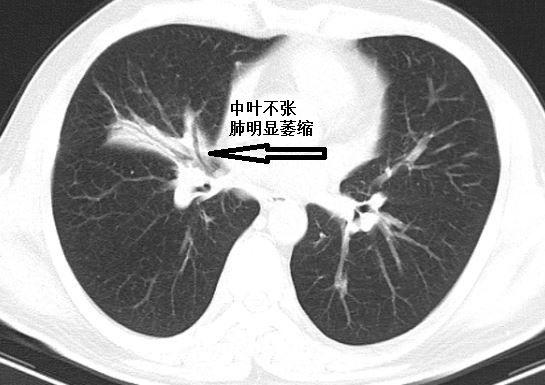

右肺中叶肺不张,右肺中叶肺不张ct图片

右肺中叶不张:前后位示:右肺模糊的密度增高影与右心缘局部分界不清

右肺中叶肺不张ct图片

肺不张ct表现

肺不张ct图片

肺不张ct表现图片